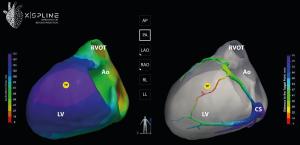

XSpline’s integrated suite of medical-grade visualization tools offers groundbreaking functionality in cardiac electrophysiology. These tools include a high-performance 3D electroanatomical viewer and an interactive navigator for LV lead placement, together with a multimodality DICOM viewer and an ECG viewer equipped with measurement capabilities. Alongside these features, proprietary algorithms enable the automatic detection of the latest activation zone and utilize unique processes to identify target points in an AI-based segmentation of CS veins structure. This system also provides automatic calculation of detailed morphology characteristics of each CS vein and its tributaries, giving the physician the ability to select patient-specific LV electrodes and delivery systems. Therefore, this comprehensive toolkit serves as an essential resource in the EP lab for various CRT implantations, aiding clinicians in achieving the highest level of CRT response through tailored, patient-specific treatment strategies. Additionally, XSpline technology includes predictive capabilities to determine who will respond to the treatment and who will not, guiding the selection of CRT implantation techniques even before the procedure begins, all with the objective of optimizing patient outcomes.

Dr. Daniel Friedman of Duke University Hospital expressed great enthusiasm for the technology, stating, "XSpline's innovative approach to cardiac mapping, including AI-based identification of the correct target zone for LV lead implantation, represents an extraordinary advancement in precision and personalization. I'm particularly excited about the potential to use this innovative technology to deepen our understanding of cardiac electrophysiology during Conduction System Pacing, a new trend in treating patients with heart failure and conduction system disorders. The ability to visualize and analyze the activation during various modes of pacing will undoubtedly open new doors in patient care and lead to more targeted, effective interventions."